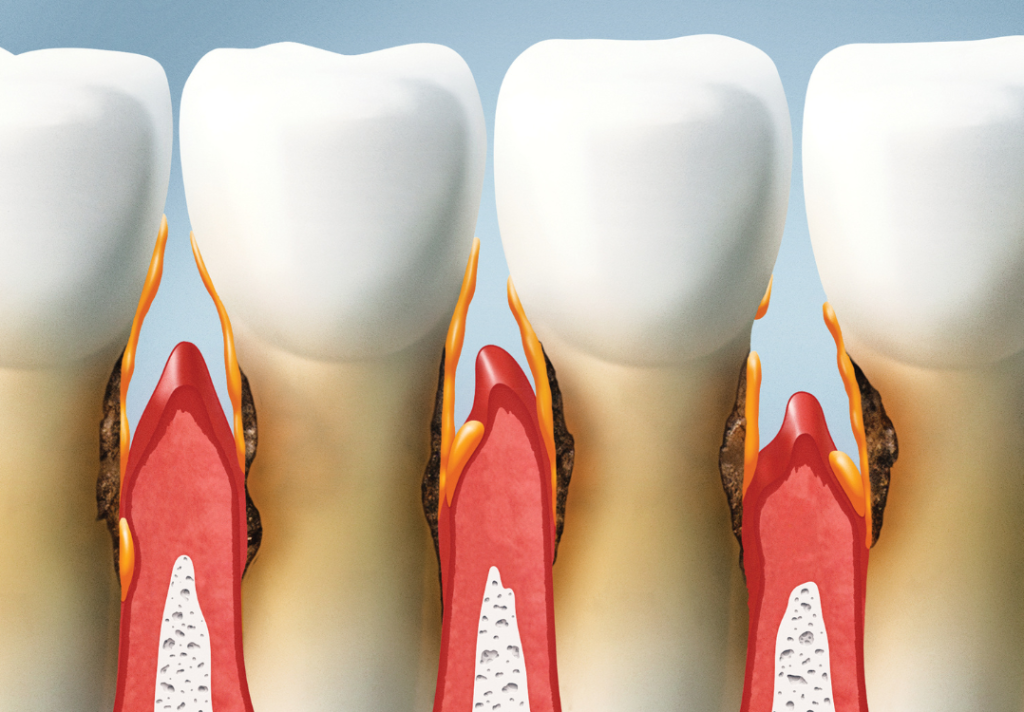

Your gums affect more than just your smile; they are living tissue. When they are inflamed or infected, bacteria and inflammatory molecules can enter the bloodstream. Even if you don’t have obvious symptoms, this harmful bacteria can quietly impact your body and raise health risks. Over time, this chronic inflammation can place extra stress on the heart, immune system, and other organs.

Gum disease is linked to heart disease, diabetes, stroke, dementia, pregnancy complications, and other systemic conditions. Our care is designed to improve your mouth and protect your overall health. Watch this video to learn more!

Gum Disease Often Starts Silently

Gum disease can begin long before you feel pain or notice bleeding. Left untreated it can lead to:

Persistent bad breath

Tooth decay along the gumline

Receding gums and bone loss

Loose teeth and tooth loss

Bacteria from your gums can travel through the bloodstream, fueling inflammation and affecting other organs.